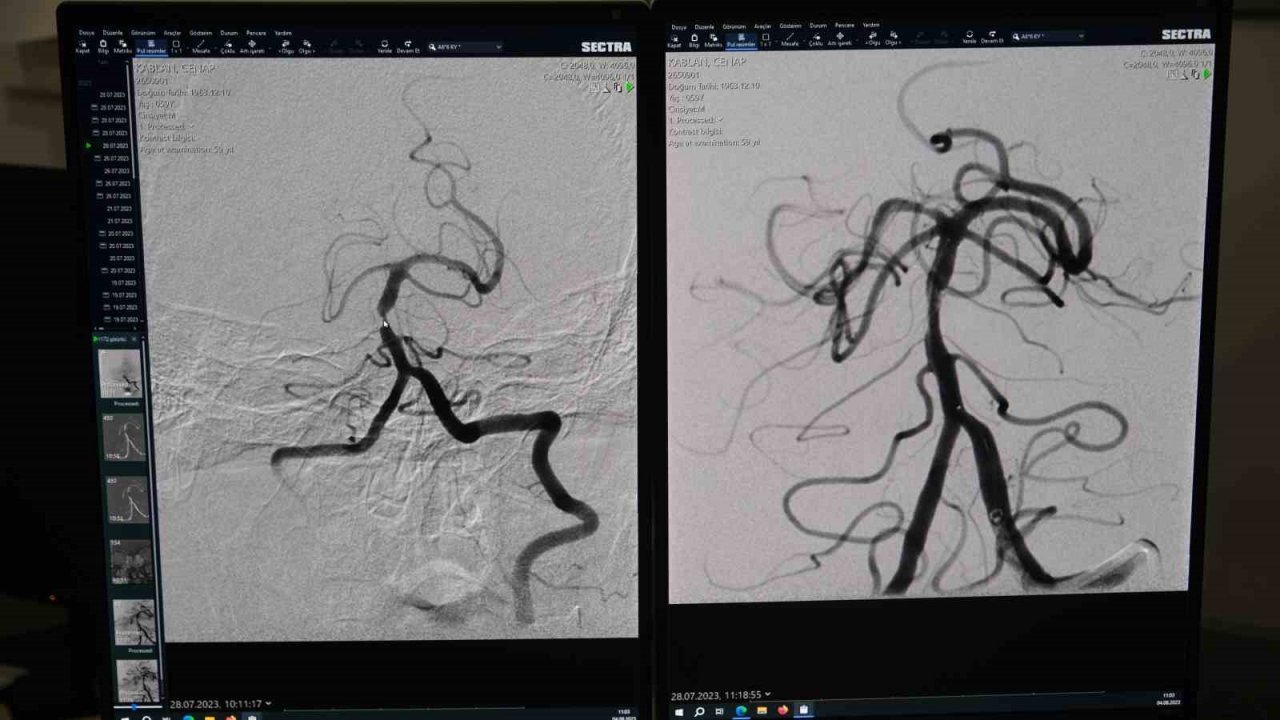

Dr. Öğr. Üyesi Yıldız, Nöroradyoloji açısından çok başarılı bir operasyon gerçekleştirdiklerini ifade ederek, "Hasta, tekrarlayan beyin inmesi atakları sebebiyle radyoloji bölümüne sevk edildi. Hastanın inme atakları ilaç tedavisine yanıt vermediği için yapılan anjiyografik incelemede beynin en önemli damarlarından biri olan beyin arka çukur ana atardamarında (baziler arterde) önemli bir darlık tespit ettik" diye konuştu.

Gerçekleştirdiği operasyona değinen Dr. Öğr. Üyesi Yıldız, "Hastanın tedavi planını yaptıktan sonra ilgili beyin damarına ulaşarak mikrokatater tekniği ile öncelikle balon yapıp damarı genişlettik. Daha sonra damarın uzun dönem daha rahat açık kalabilmesi için bu bölgeye bir stent yerleştirdik. Hastamız şu an sağlıklı bir şekilde nöroloji servisinde yatmaktadır. Hastamızın işlem öncesi sağ kol ve bacağında güçsüzlük vardı. Bacağındaki güçsüzlük tedavi sonrasında daha iyi bir duruma geldi. Kolu da ilerleyen dönemde fizik tedaviyle daha iyi bir hale gelecek. Kendisine geçmiş olsun dileklerimizi iletiyoruz" şeklinde konuştu.